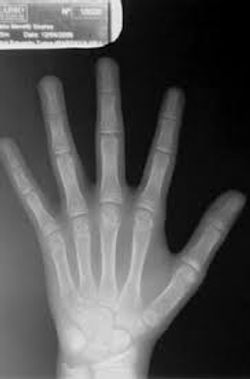

O que é o exame: estudo radiográfico da mão e punhos em incidência ântero-posterior, para posterior comparação com radiografias padronizadas para a faixa etária e sexo.

Para que serve: determinação radiológica da idade óssea, valiosa na determinação da idade fisiológica e do potencial de crescimento, bem como na previsão da altura, quando adulto. As discrepâncias entre a idade fisiológica (segundo a maturidade do esqueleto) e a idade cronológica são importantes do ponto de vista clínico, pois podem ser provocadas por moléstias da infância e distúrbios que provocam anormalidades do crescimento. A deficiência de hormônio de crescimento e de hormônios tireóideos causa o retardo da idade óssea mais grave. Condições, como tireotoxicose, puberdade precoce e, até mesmo, a obesidade, avançam a idade óssea.

Fundamento: a estimativa da idade óssea fundamenta-se na existência ou não de centros de ossificação e na configuração deles.